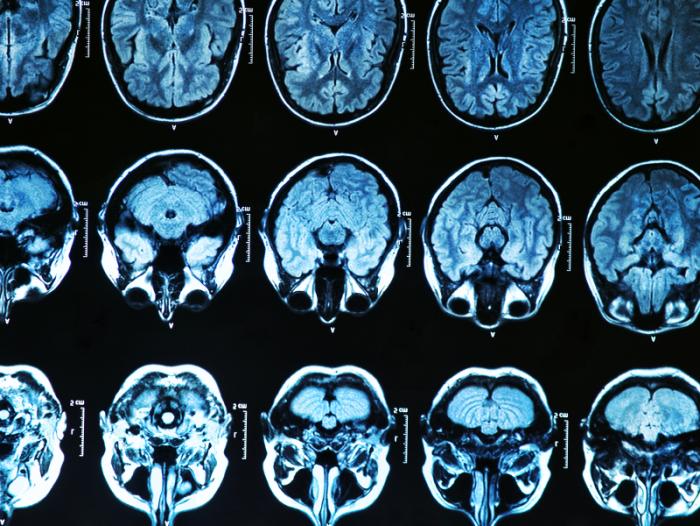

Genengnews.com reports: Researchers from 16 institutions across the U.S., Canada, England, Scotland, and Australia have now analyzed genetic, transcriptomic, and proteomic data from infected individuals, and from studies in cell cultures, to link T. gondii infection with a number of brain disorders, including epilepsy, Alzheimer’s and Parkinson’s diseases, and even some cancers. “This study is a paradigm shifter,” stated co-author Dennis Steindler, Ph.D., director of the Neuroscience and Aging Lab at the Jean Mayer USDA Human Nutrition Research Center on Aging at Tufts University. “We now have to insert infectious disease into the equation of neurodegenerative diseases, epilepsy, and neural cancers. At the same time, we have to translate aspects of this study into preventive treatments that include everything from drugs to diet to lifestyle, in order to delay disease onset and progression.”

Prior research has indicated that T. gondii infection in rodents and in primates can cause subtle behavior changes, including loss of the animals’ aversion to the smell of the urine of their natural predators. Some epidemiological studies in humans have linked T. gondii infection with neurological disorders such as Parkinson’s and Alzheimer’s diseases. However, this type of study can’t provide any information on gene networks in the human brain that are altered by the parasite, and which might provide insights into how to cure or prevent such diseases, Dr. Steindler and colleagues write in their published study in Scientific Reports, which is entitled “Toxoplasma Modulates Signature Pathways of Human Epilepsy, Neurodegeneration & Cancer.”

Using data from the National Collaborative Chicago-Based Congenital Toxoplasmosis Study (NCCCTS), which has followed 246 congenitally infected persons and their families since 1981, the researchers carried out what they called a “comprehensive systems analysis,” to identify parasite-related biomarkers and evaluate their potential impact. The team also looked at the effect of T. gondii infection in cultured primary neuronal stem cells, to evaluate gene expression and protein signatures. The study combined host genetics proteomics, transcriptomics, and circulating microRNA data to generate a model of how T. gondii affects the human brain.